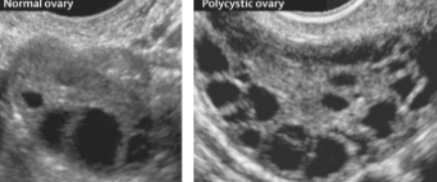

Síndrome dos Ovários Policísticos

Achados no USG

Cistos anecoicos